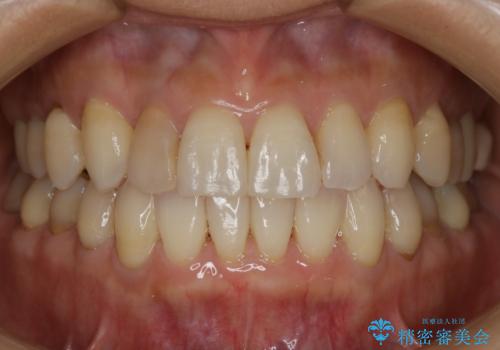

![[突き出た前歯を引っ込めたい] ワイヤー矯正とマウスピース矯正の併用治療の症例 治療後](https://seimitsushinbi.jp/wp/wp-content/uploads/2024/08/IMG_9725-500x350.jpg?v=1723179307)